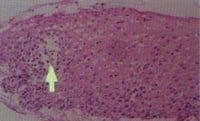

El diagnóstico de metaplasia intestinal especializada fue realizado por identificación de epitelio columnar con células calciformes y la captación del colorante con azul alciano (39)(Figuras 1 y 2);lo contrario,permitió clasificar el caso como metaplasia intestinal no especializada (40).

Figura 1. Metaplasia intestinal

especializada .

Figura 2. Metaplasia intestinal